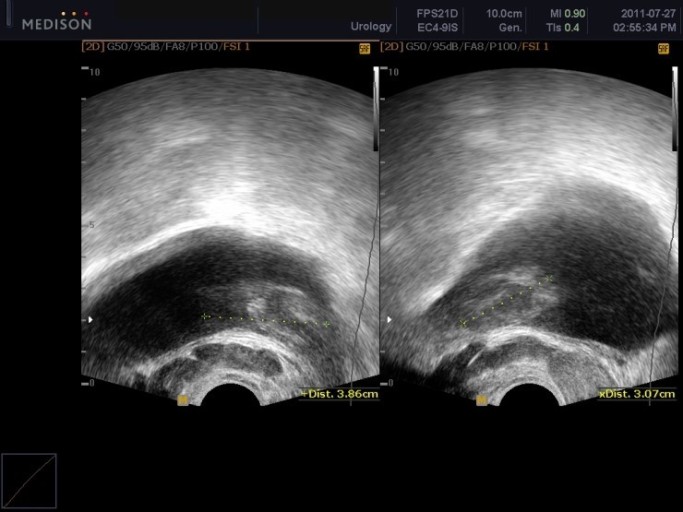

- 정기 검진 필수: 50세 이상 남성은 **매년 혈액 검사(PSA, 전립선특이항원)**와 직장수지검사를 통해 조기 검진을 받는 것이 중요합니다. 가족력이 있다면 40대부터 검진을 시작해야 합니다.